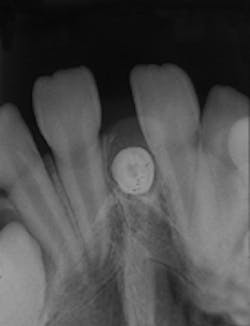

Mesiodens

1. Identify the most common location for the mesiodens.

2. Identify the radiographic appearance of the mesiodens.

3. Identify the best method to diagnose a mesiodens.

4. Identify the true statement concerning the mesiodens.

CASE 1: 1 = b; 2 = b; 3 = d; 4 = a